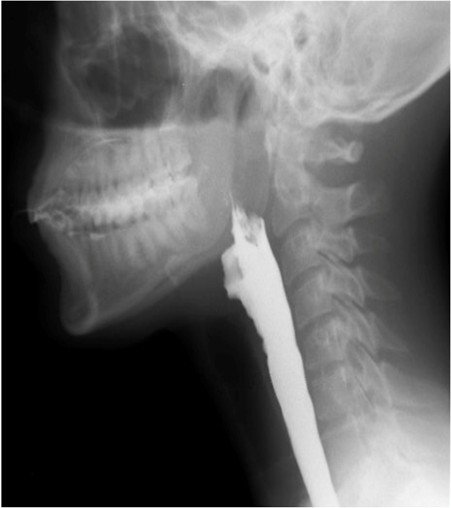

Adequate elevation of the hyoid-laryngeal complex is a key factor in achieving effective glottic closure and this can be evaluated by assessing the maximum vertical displacement of the hyoid. Under normal conditions the hyoid should reach the level of the ramus of the mandible, but this has been shown to be variable with bolus size and is more reliably seen with the deglutition of big boluses.28

Epiglottic movement can be difficult to evaluate on videofluoroscopy as its assessment relies on indirect images from the movement of contrast through the pharynx, but complete laryngeal closure may be inferred when no air or contrast accesses the laryngeal vestibule. (Fig. 9)

Figure 9: Under normal circumstances, the laryngeal inlet closes completely and no contrast is seen on the laryngeal vestibule. Notice the adequate elevation of the hyoid bone which reaches the level of the ramus of the mandible.